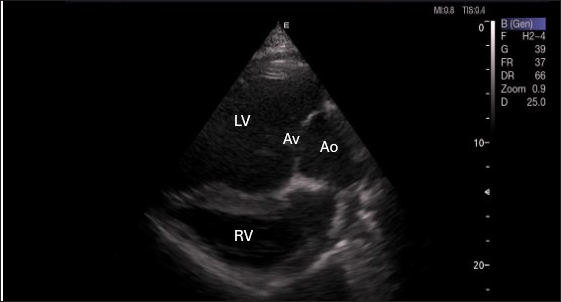

By positioning the probe perpendicularly in the fourth intercostal space or longitudinally in the fifth space with a little clockwise rotation, the interventricular septum, ventricles, and atria could be observed in the caudal long-axis four-chamber view (Fig. 1). From this vantage point, all camels could be seen to have a left ventricle, mitral valve, interventricular septum, right ventricle, and tricuspid valve. Figure 2 shows that in the short-axis image of the cardiac ventricles obtained with a little clockwise rotation at the 4th ICS, only the right ventricle, interventricular septum, and left ventricle were visible. Here, the dimensions of all camel heart were measured in M mode. The right parasternal two-dimensional short-axis pictures of the heart’s base in the first frame were used to determine the LA/Ao ratio, by applying 2D and M mode (Figs. 3 and 4). Despite some difficulties, we successfully acquired a pulmonary image by attempting to acquire the right ventricular outflow tract for the right short axis at the level of the great vessels.

Fig. 1. Right parasternal longitudinal axis (systole) of 16 years racing camel showing Lv=left ventricle, Rv=right ventricle, Ivs=Inte3r ventricular septum, Mv=mitral valve, and Tv=tricuspid valve.

Figure 5 shows an image of the ventricles, atria, and interventricular septum in the caudal long-axis four-chamber view acquired by positioning the probe perpendicularly in the fourth intercostal space or longitudinally in the fifth intercostal space with a little clockwise rotation. Every camel had a perfectly normal heart anatomy, including ventricles, tricuspid valve, mitral valve, and atria on both sides. During the fourth ICS image of the LVOT, the probe was turned slightly further cranially and twisted somewhat counterclockwise (Fig. 6). No camel is complete without an oblique aortic cross-section.

Fig. 6. Left parasternal long axis of 18 racing camel showing LOVT=left ventricular outflow tract. LV=left ventricle, Av=aortic valve, Ao=aortic artery, Rv=right ventricle.